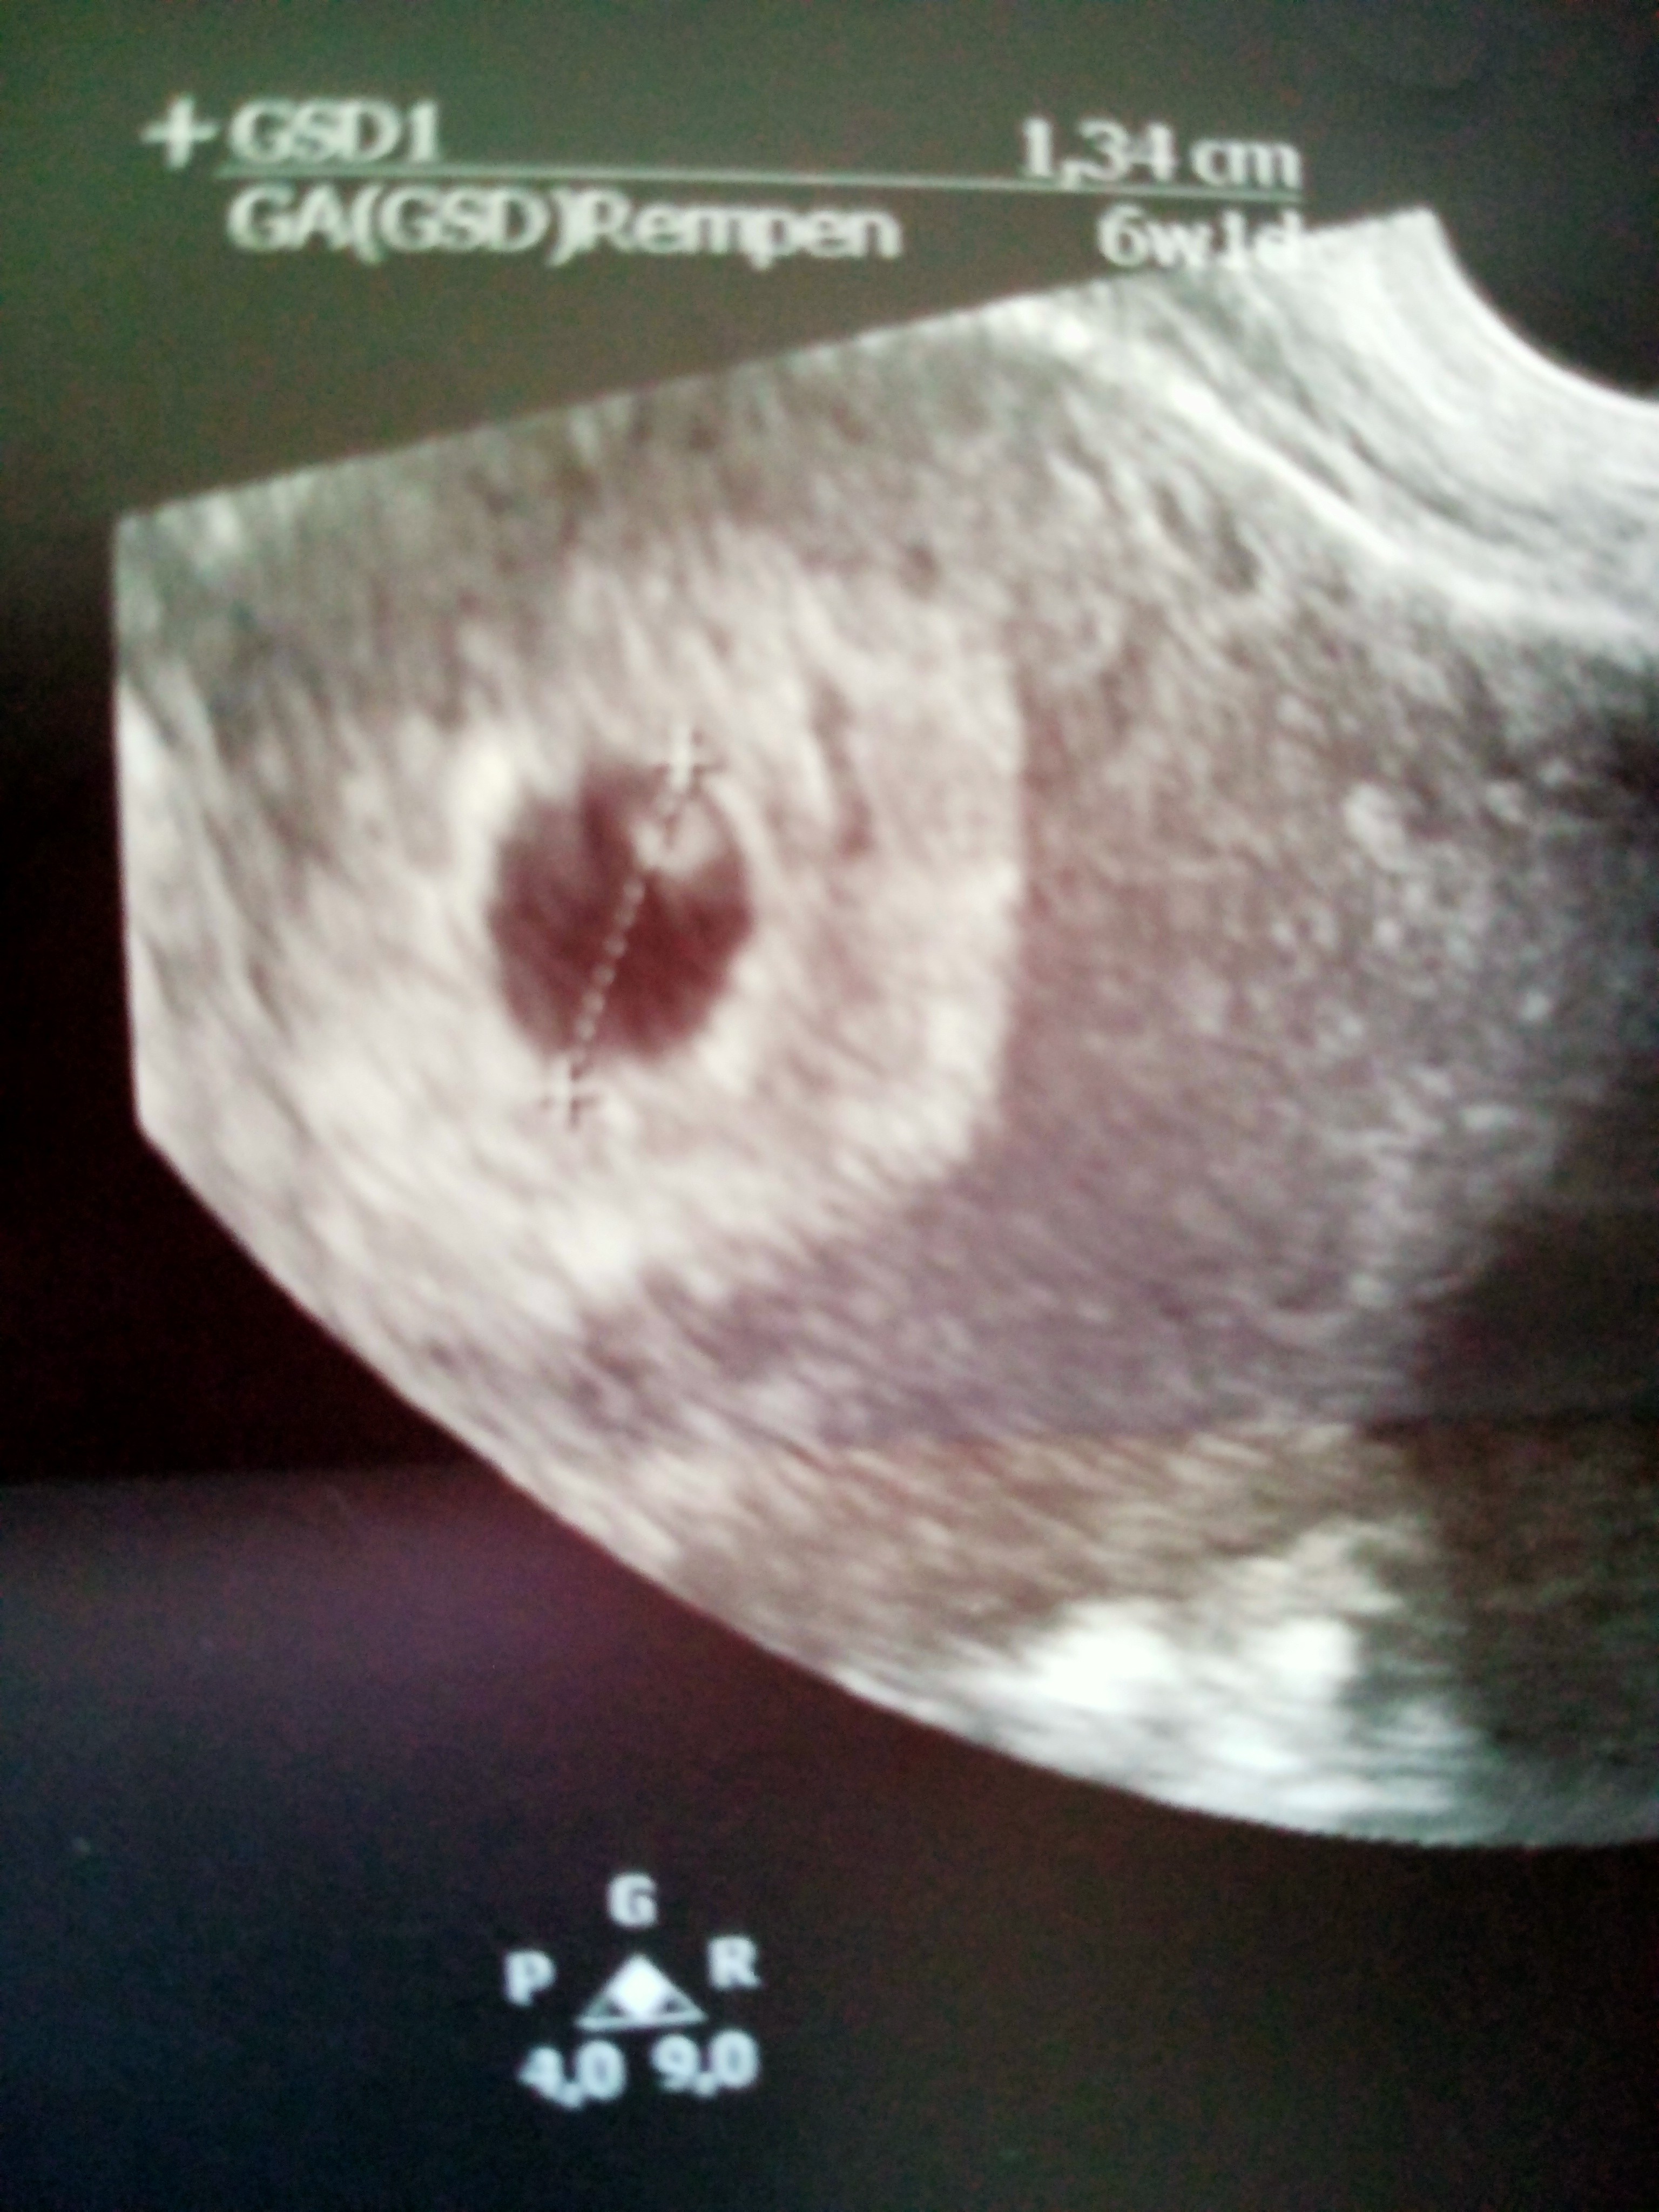

Dziewczyny czy miałyście tak że według ostatniej miesiączki jestem w 6 tygodniu , i lekarz powiedział że echo zarodka słabo wyczuwalne czy mam się bać ? Czy po prostu może okazać się że ciąża jest młodsza ? Lekarz nie powiedział mi nic konkretnego tylko tyle że musimy teraz patrzeć jak to będzie się rozwijać

Słabo widoczne przepraszam

Jeśli owulacja nie była monitorowana to mogła być później, a mogło być też tak, że zagnieżdżenie było późno. Nie ma się co martwić niepotrzebnie.

Właśnie narazie nie biorę tego pod uwagę cieszę się że jest moja gwiazdeczka ❤️ bo we wtorek byłam u innego lekarza to powiedział mi że podejrzewa puste jajo aż mnie coś skręcało mówię nie możliwe , cała noc się martwiłam a wczoraj dowiedziałam się że jest ❤️ zobaczcie jaką jest różnica sprzęt a sprzęt 😊 we wtorek było robione USG normlanie a z wczoraj jest dopochowo